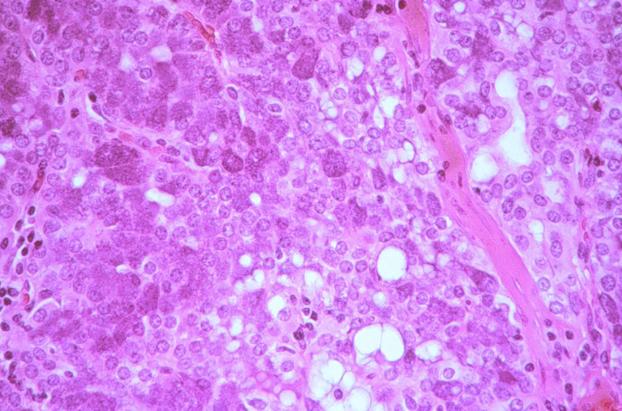

What is the most likely diagnosis for this brain lesion?

A) arteriovenous malformation

B) glioblastoma multiforme

C) infarction

D) pilocytic astrocytoma

E) radiation necrosis